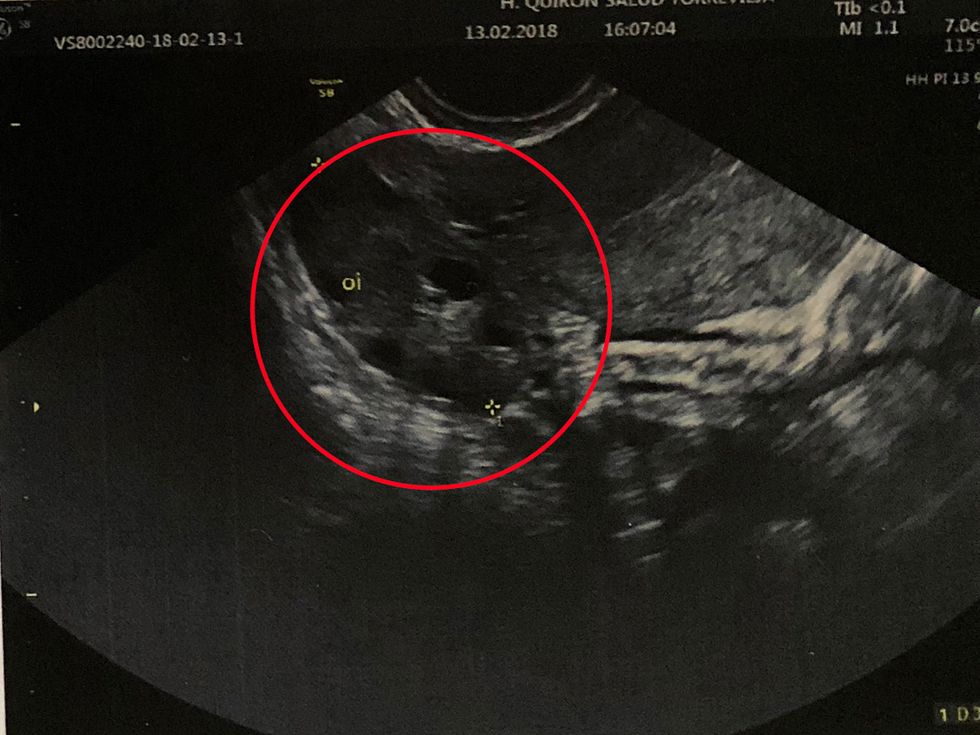

“At a check-up, they said my levels had risen, so I had an ultrasound scan at Hospital Quirón Torrevieja, in Alicante, a private hospital, to be seen quicker and a growth was spotted.”

“Looking at the scan on the screen, I could see the tumor. It was like a cluster of grapes and doctors believed a small amount had continued to grow after the first tumor was removed.”